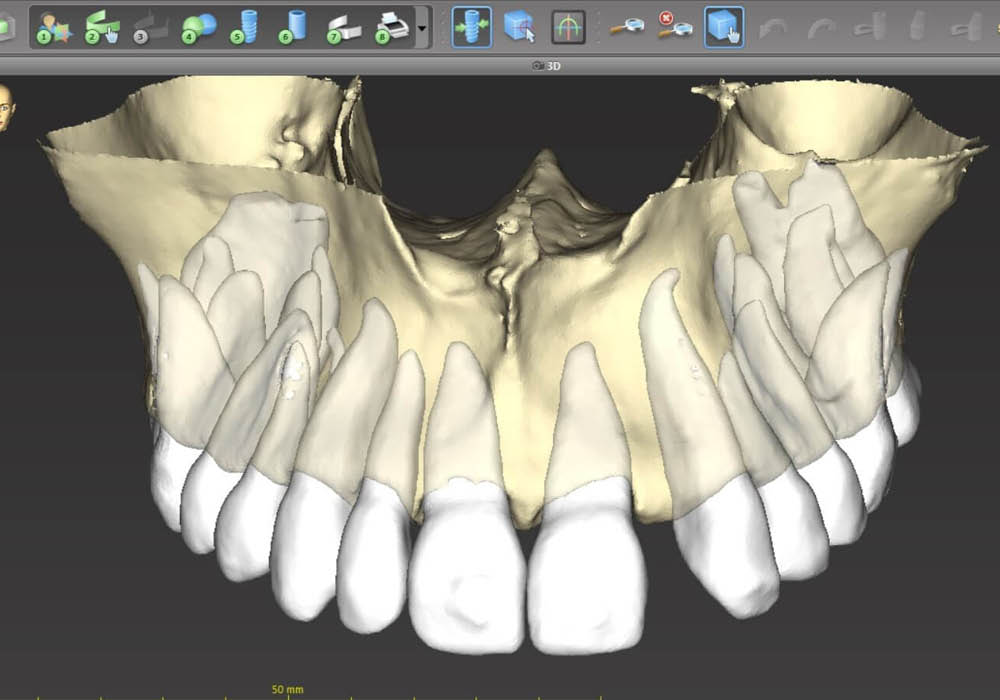

2. Segmentazione DICOM con supporto AI

La segmentazione dei dati CBCT è stata effettuata partendo da un file DICOM.

L’utilizzo dell’intelligenza artificiale ha permesso di automatizzare la separazione e la ricostruzione tridimensionale delle strutture anatomiche, facilitando l’elaborazione e garantendo maggiore precisione nella valutazione iniziale.